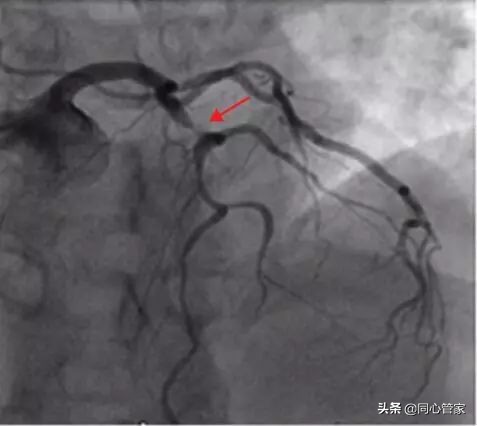

冠脉造影:在平时,冠脉造影是诊断冠心病最常用有效的方法,但它只是一个二维平面图像存在一定的局限性,没法让我们了解血管里面发生的情况。

OCT:OCT检查是一种影像学检查,对于判断冠动脉的斑块形成及狭窄程度,包括支架置入手术前、术后血栓的形成或者斑块的形成,支架置入手术后的疗效等,能做出综合指导、判断,这对冠心病患者的疗效有着重要意义。